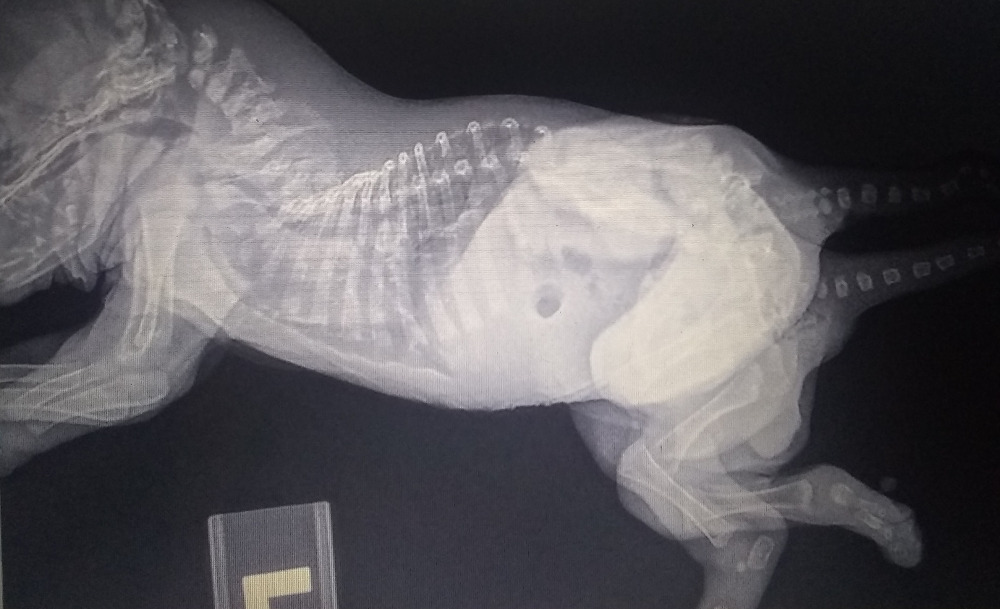

"Шкіпер прожила довше, ніж будь-яка інша собака з таким вродженим станом, - розповіли лікарі. - У неї одна голова і грудна клітка, але дві тазові області, дві системи сечовивідних шляхів, дві репродуктивні системи, два хвоста і шість лап. У дослідженнях немає інформації про те, щоб такі цуценята народжувалися живими".

Лікарі припустили, що дві яйцеклітини в утробі матері Шкіпер не розділилися, давши життя унікальному цуценяті. Всього в посліді було 9 цуценят, і більше ні в одного немає аномалій.

Обнадіює, що органи Шкіпер в чудовому стані, а всі її лапи рухаються і реагують на подразники, як у нормального цуценяти. Поки лікарі не планують робити реконструктивну операцію і не бачать причин присипляти щеня, оскільки воно нормально розвивається, не має проблем із харчуванням і травленням.